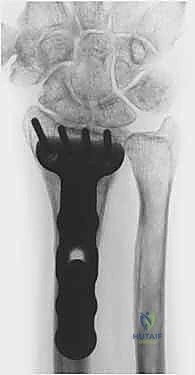

5. التثبيت بصفائح التيتانيوم (Internal Fixation)

للحفاظ على الوضع الجديد والمثالي للعظم، يتم استخدام صفائح تيتانيوم متقدمة ذاتية الغلق (Volar Locking Plates). هذه الصفائح مصممة تشريحياً لتلائم شكل الكعبرة، وتوفر تثبيتاً قوياً جداً يسمح للمريض ببدء تحريك أصابعه في اليوم التالي للعملية.